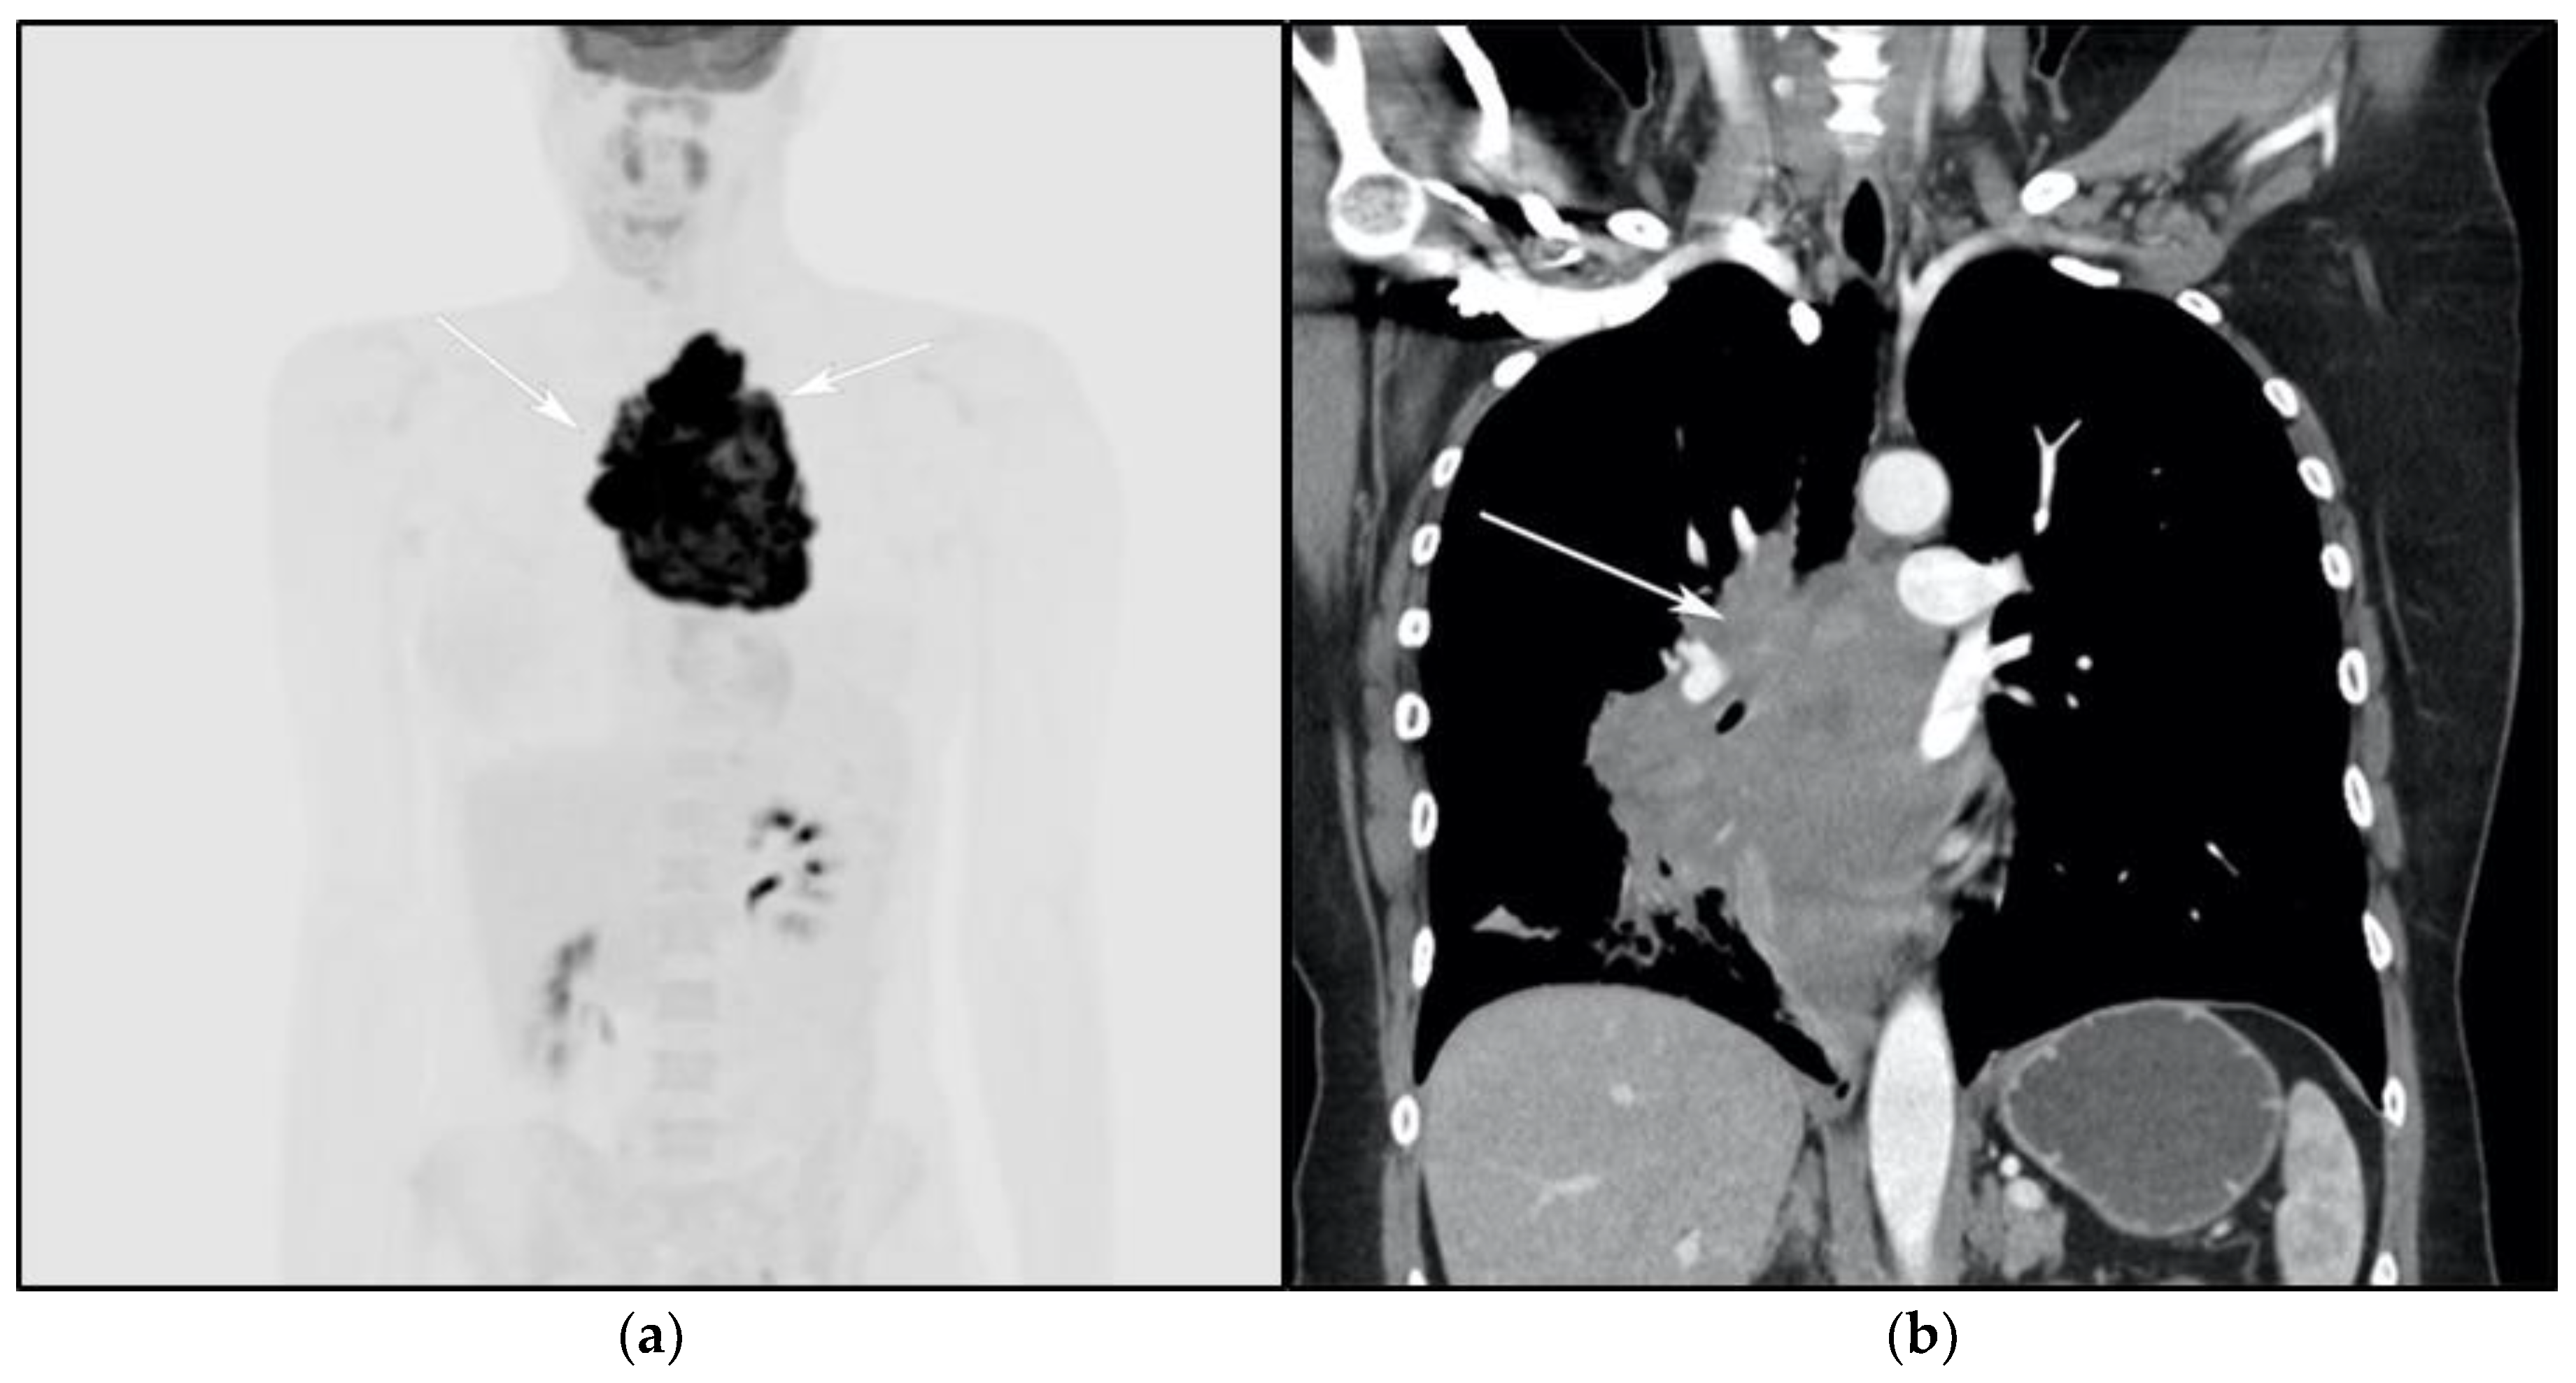

The differential diagnosis of PMLBCL includes other anterior mediastinal masses such as CHL, germ cell tumors, and large thymic tumors, which can display necrosis and calcifications on CT [32]. Differentiation between PMBCL and CHL is not possible based on imaging findings alone. More aggressive clinical behavior such as superior vena cava syndrome may help distinguish PMBCL from CHL [33] (Figure 5).

Figure 5.

A 24-year-old female presenting with cough and dyspnea with plethora of the face. (a) Maximal intensity projection (MIP) FDG PET/CT shows hypermetabolic anterior mediastinal mass (white arrows) with no other sites of disease involvement in the body. (b) Coronal contrast-enhanced CT image shows significant vascular and airway compromise by an ill-defined anterior mediastinal mass (white arrow). Biopsy-proven primary mediastinal B-cell lymphoma. Main differential diagnosis would be Hodgkin’s lymphoma. However, unlike in Hodgkin’s lymphoma, primary mediastinal B-cell lymphoma often shows frequent invasion of the mediastinal vessels, frequently resulting in superior vena cava syndrome.

The use of 18F-FDG PET/CT is essential in the evaluation of patients with PMLBCL to reveal sites of disease not visible on CT and to provide more accurate staging and radiation field planning (Figure 6). 18F-FDG PET/CT may also be beneficial for restaging after chemotherapy and/or radiotherapy, or when relapse is suspected [34]. Negative 18F-FDG PET/CT after two or four cycles of chemotherapy has a negative predictive value and may predict excellent outcome in patients, achieving complete response without relapse. Patients who have residual activity equal to or higher than liver activity after immunochemotherapy treatment are more likely to relapse. In such instances, the addition of radiotherapy to the treatment regimen should be considered to avoid relapse in those high-risk patients. Relapse usually occurs within 1 year and is more likely to be widespread, involving distant extranodal sites such as the CNS, liver, kidneys, adrenal glands, GI tract, ovaries, and pancreas. Late relapses are very uncommon [35]. 18F-FDG PET/CT can also efficiently assess post-treatment response, differentiating between necrotic or fibrotic tissue and residual masses containing viable tumor [33,36]. There are various potential challenges to 18F-FDG PET/CT post-treatment implementation, including false-positive results secondary to thymic rebound hyperplasia, specifically seen in the young population. This can be limited by increasing the interval between treatment and imaging. Additionally, MRI can be helpful in those cases, and high signal on T1 in phase imaging with loss of signal on the out of phase sequences is consistent with thymic rebound hyperplasia (Figure 7 and Figure 8) [34,37].

Figure 6.

Imaging in a different patient with known diagnosis of primary mediastinal B-cell lymphoma. (a) Axial FDG PET/CT images show the hypermetabolic anterior mediastinal mass (white arrows), and there is also central areas of absent metabolic activity within the mass (red arrow), correlating with areas of fibrosis, a finding that is essential in prebiopsy planning to avoid false negative results. (b) Axial FDG PET/CT images show hypermetabolic right upper paratracheal nodes (white arrows) and several additional hypermetabolic pulmonary and pleural-based nodules within right upper lung (red arrows). (c) H&E section shows that the tumor is composed of large, atypical cells with reniform or multi-lobulated nuclei with abundant clear cytoplasm. Note the lymphoma cells are compartmentalized by the prominent sclerotic bands of fibrosis. (Original magnification 400x, H&E stain).